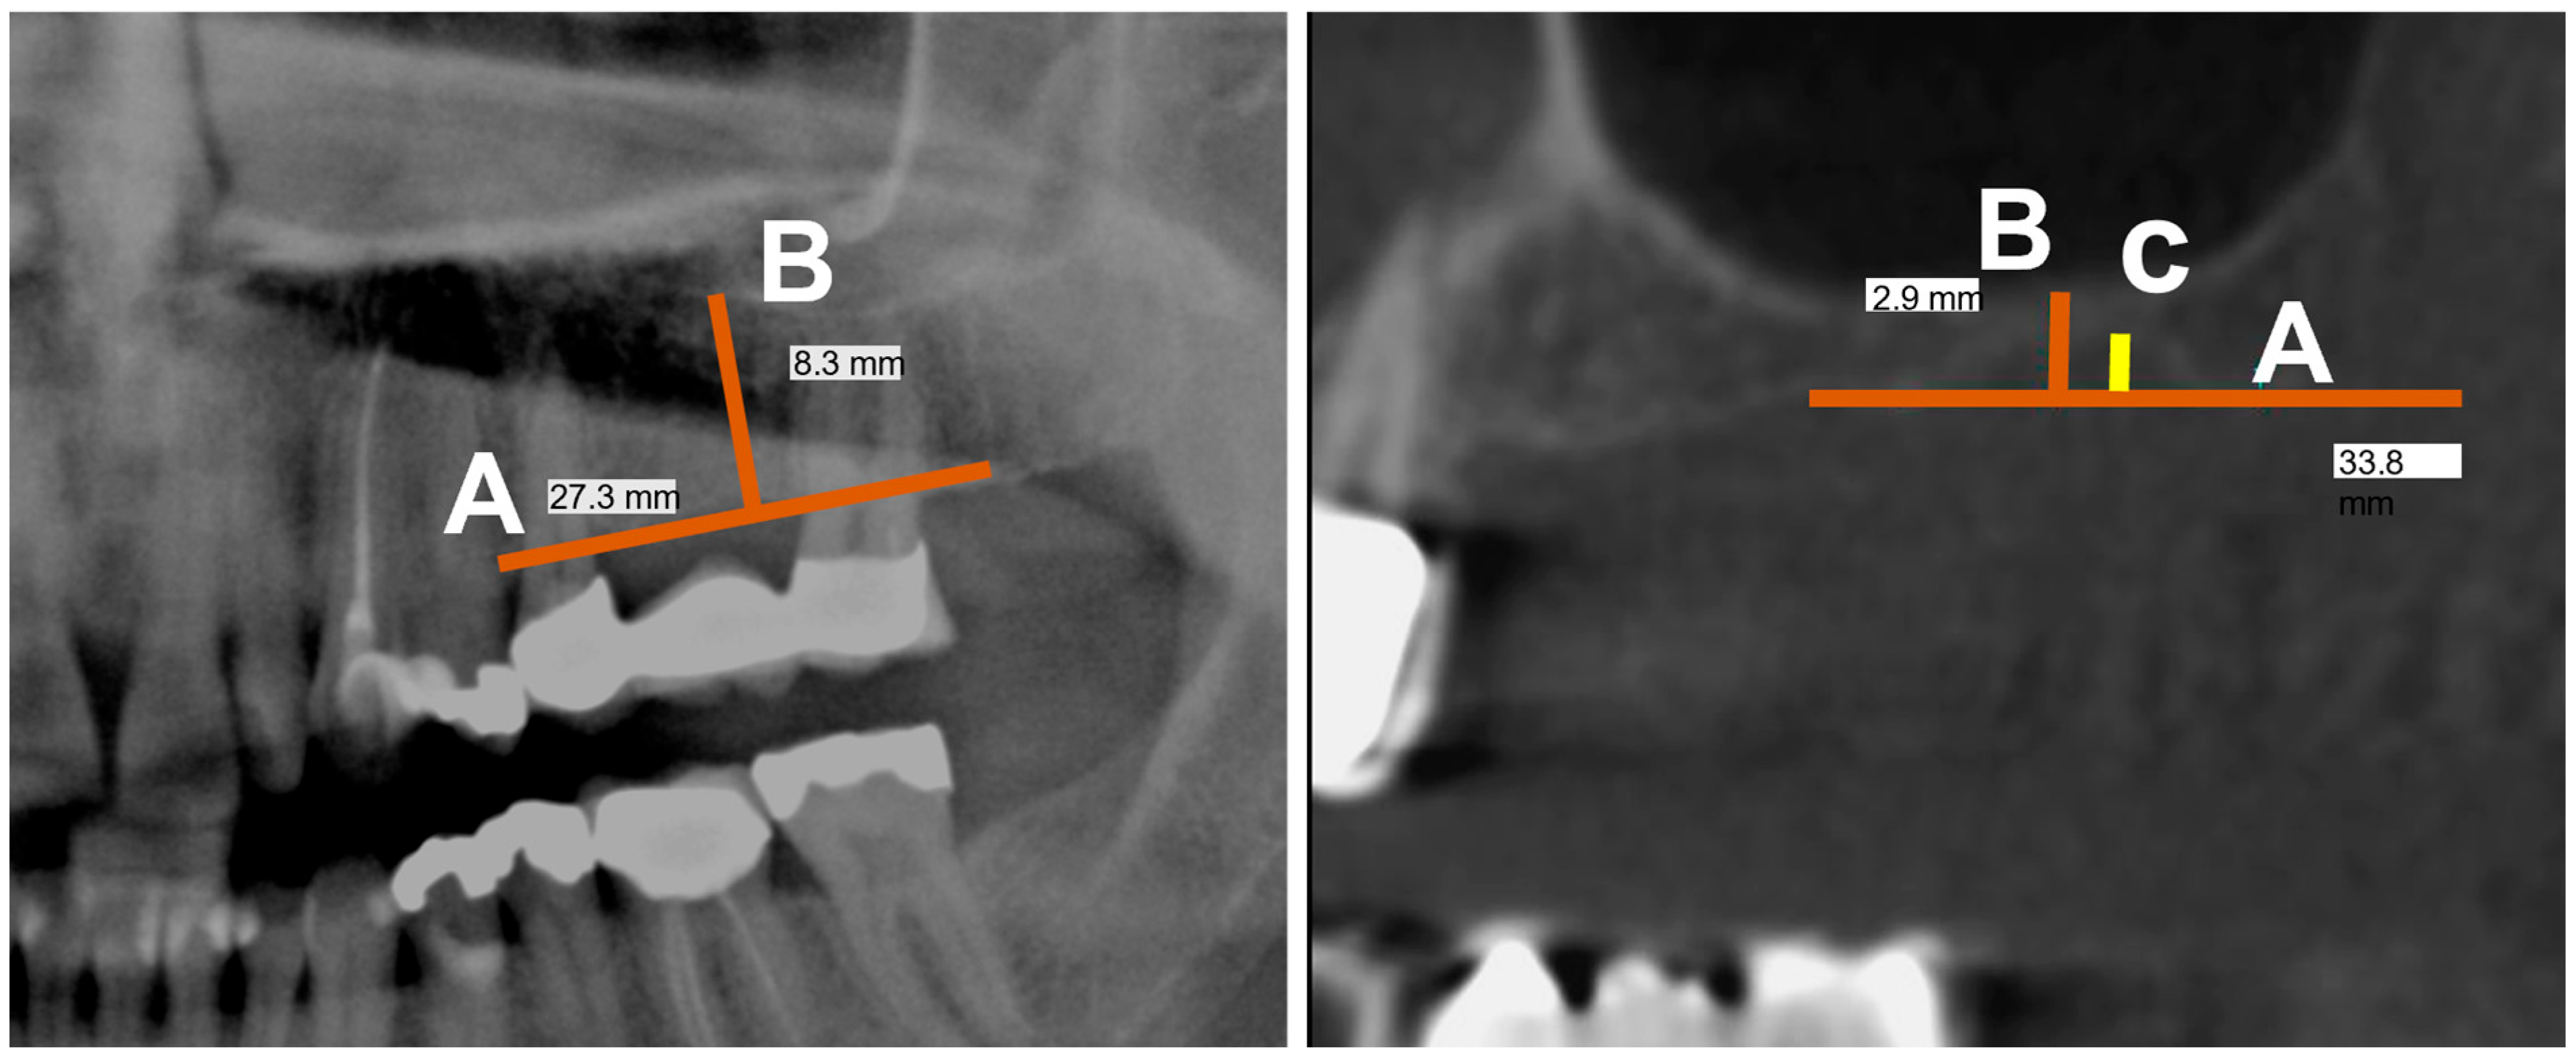

The following procedure was chosen for patients who were either completely edentulous or edentulous only in the defined area and had no vertical bony defects. In these cases, an auxiliary line was formed that was spanned by two reproducible points on the alveolar ridge. The measuring distance was determined using a geometrically constructed vertical distance, defined as the perpendicular distance between the auxiliary line and the sinus floor (Figure 4, left). This method improves both reproducibility and error susceptibility.

In the case of vertical defects in the defined area, the procedure was similar. Here, in addition to the previously described measuring section, the defect height that can occur after tooth extraction was measured as a geometrically constructed vertical distance between the auxiliary line and the defect roof (Figure 4, right).

Figure 4. (left) PAN image of the maxilla without vertical defects showing the measurement in the edentulous region of the auxiliary line (A) and the perpendicularly formed line (B) on this plane. (Right) CBCT image of the maxilla with vertical defects showing measurement of the auxiliary line (A) and the perpendicularly formed line (B) on this plane, as well as the defect height (C).